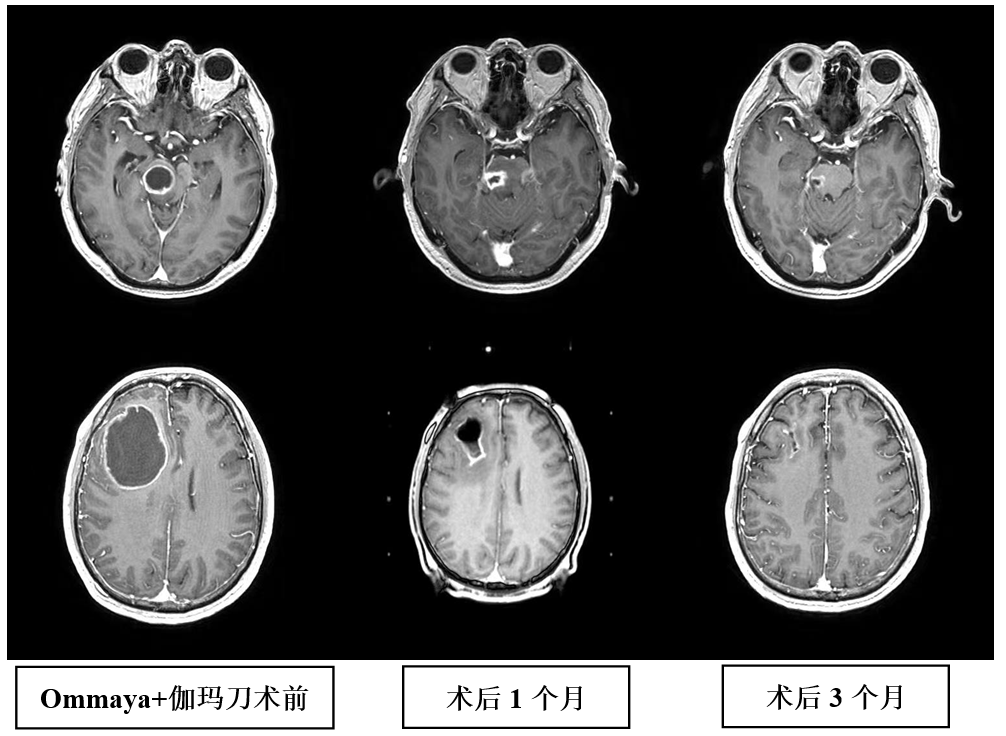

1、伽玛刀联合Ommaya囊穿刺引流术治疗巨大囊性脑转移瘤。穿刺引流可迅速改善占位效应,减少神经功能损害,结合伽玛刀治疗,提高病灶的局控率,当囊性病灶位于脑干等重要功能部位时,治疗效果更加明显。2018年12月,我们在上海脑转移瘤高峰论坛分享了此项经验。